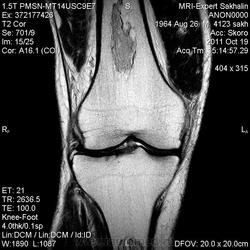

- В ранней стадии заболевания - отек (гипоинтенсивный на Т1-взвешенном изображении и гиперинтенсивный на Т2-взвешенном изображении)

- Позднее отграничение вдоль периферии пораженной кости (гипоинтенсивное на Т1 - взвешенном изображении; на Т2-взвешенном изображении - гиперинтенсивная линия по направлению к зоне некроза, соответствует грануляционной ткани)

- Гипоинтенсивная линия по направлению к здоровой кости (склероз, фиброз): признак двойной линии

- Накопление контрастного вещества периферической зоной

- При застарелых инфарктах кости интенсивность сигнала зоны некроза эквивалентна жировой ткани

- Периферическая зона типично извилистая, напоминает гирлянду.

а, b Инфаркт зрелого костного мозга. (а) Сагиттальная протонная плотно-взвешенная МРТ с подавлением МР-сигнала от жировой ткани. Изображение демонстрирует гирляндовидный склеротический край и центральный участок с сигналом жирового костного мозга. Множественные некротические зоны расположены преимущественно в метадиафизальной области, однако несколько находятся непосредственно рядом с суставом, в связи с чем имеется риск уплощения суставных поверхностей;